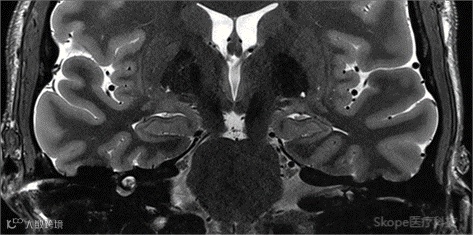

Sagittal T2 TSE

pTx有效改善了小脑区域图像均匀性。